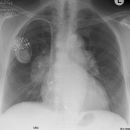

Mitralklappenersatz